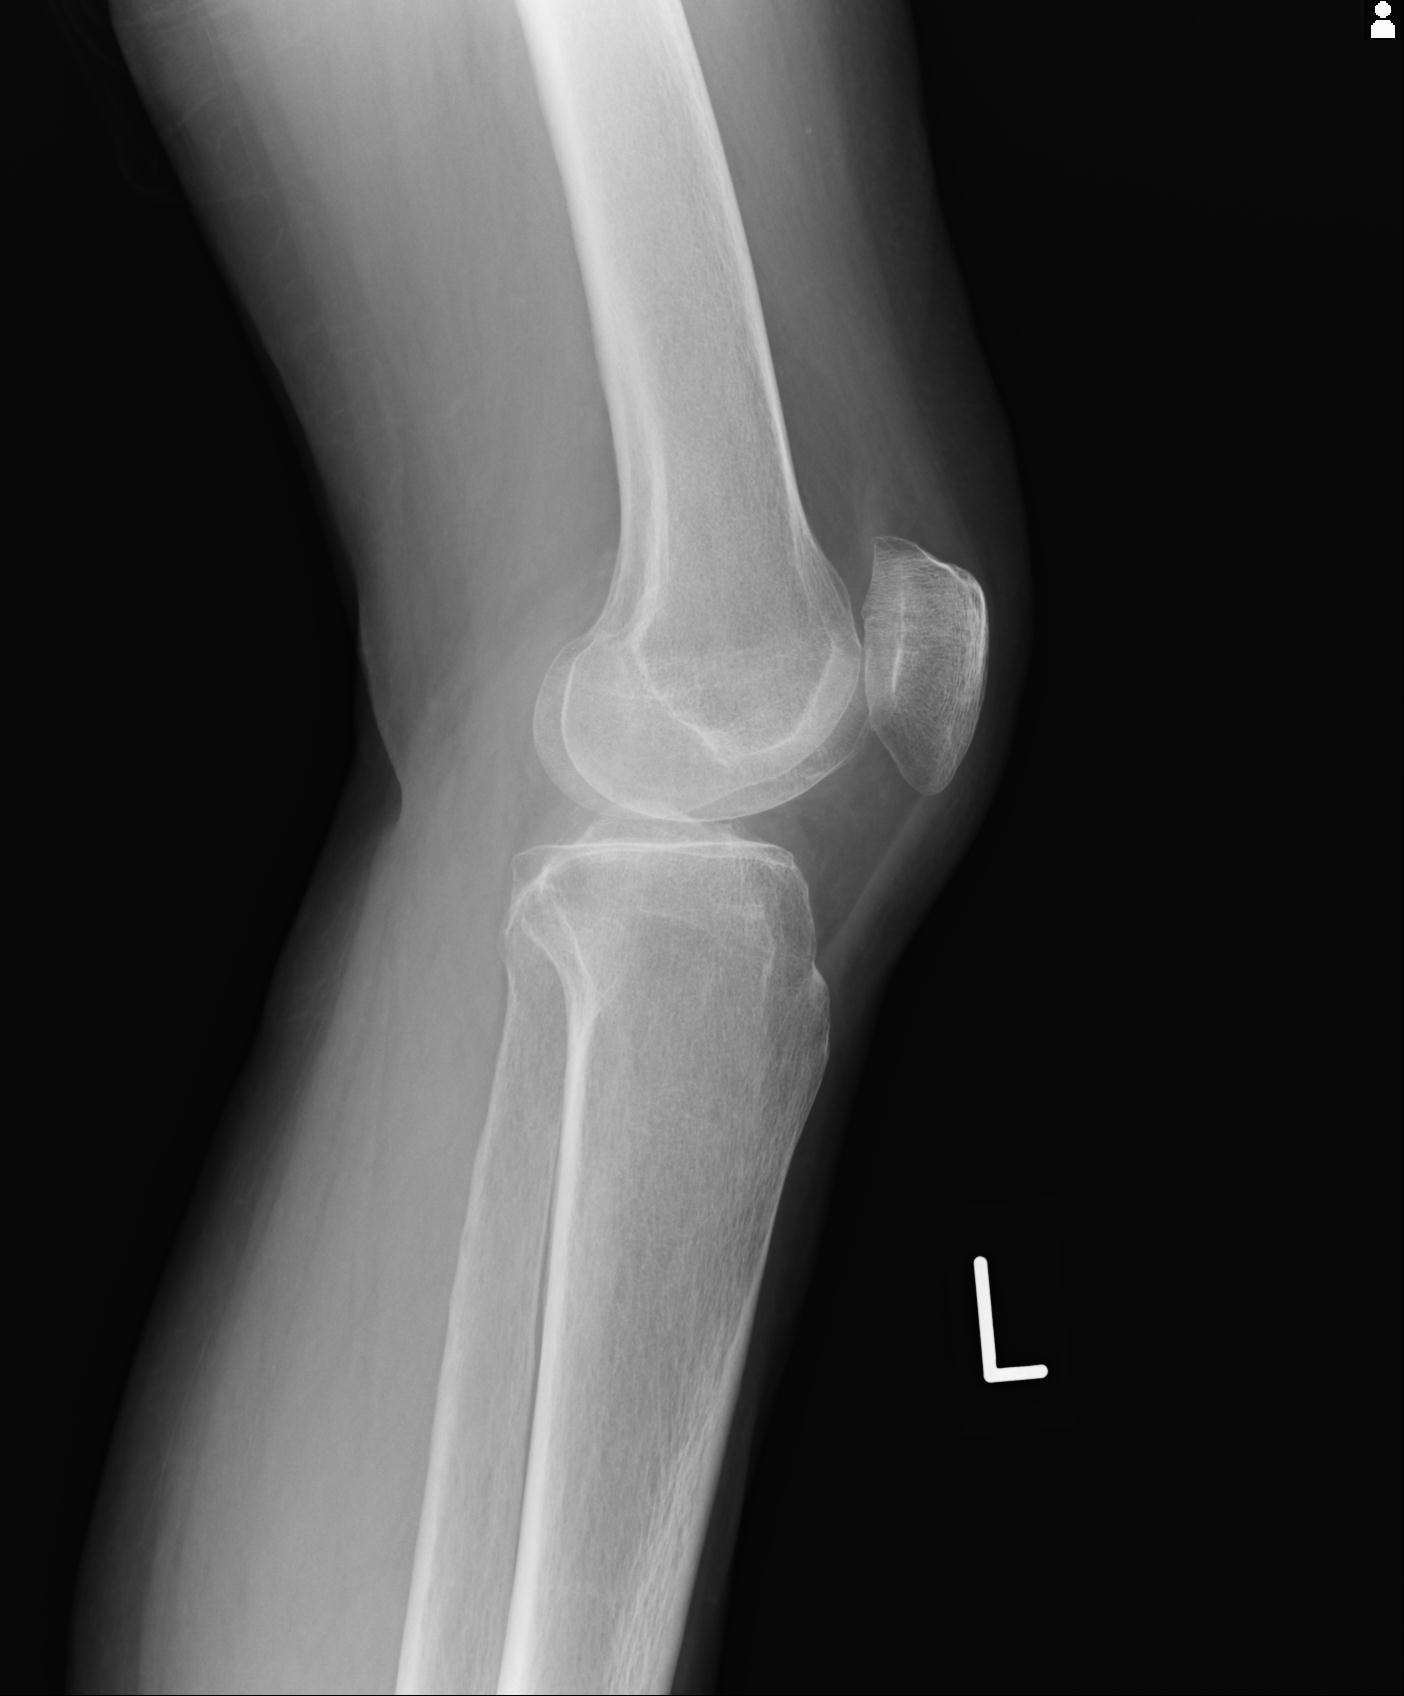

91983 11/16 左膝 2R 11/18 2R 55歳男性 脛骨骨切り術